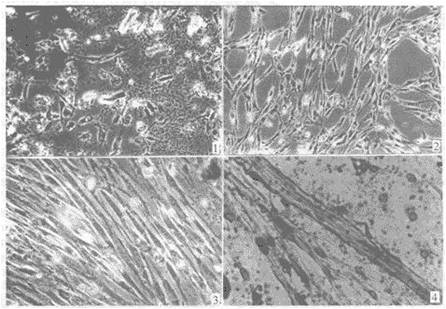

光鏡下的間充質(zhì)干細(xì)胞 電鏡下的間充質(zhì)干細(xì)胞

肌肉衛(wèi)星細(xì)胞 熒光染色的肌肉衛(wèi)星細(xì)胞